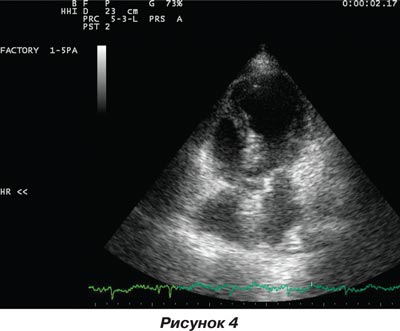

При ЭхоКГ выявлен обширный дефект межжелудочковой перегородки, сопровождающийся массивным потоком из левого в правый желудочек сердца с развитием выраженной легочной гипертензии, что и явилось причиной развития кардиогенного шока (рис. 4, 5).